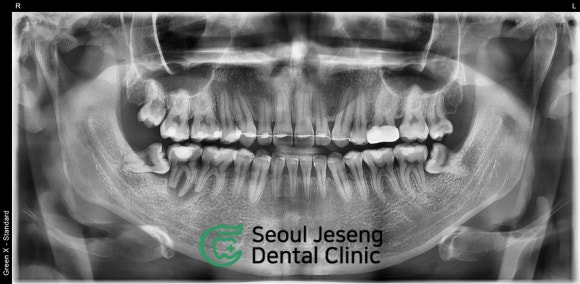

치료 전 후 비교, 뼈가 재생되었어요!

초기 염증으로 치아 뿌리 주위의 뼈가 많이 상실되어 있었습니다.

뿌리를 둘러싸고 있는 까만 공간만큼 뼈가 상실된 것이죠.

하지만 아래의 사진을 보시면,

뿌리 주위로 새로운 뼈가 (짙은 회색)이 재생된 것을 확인할 수 있습니다!